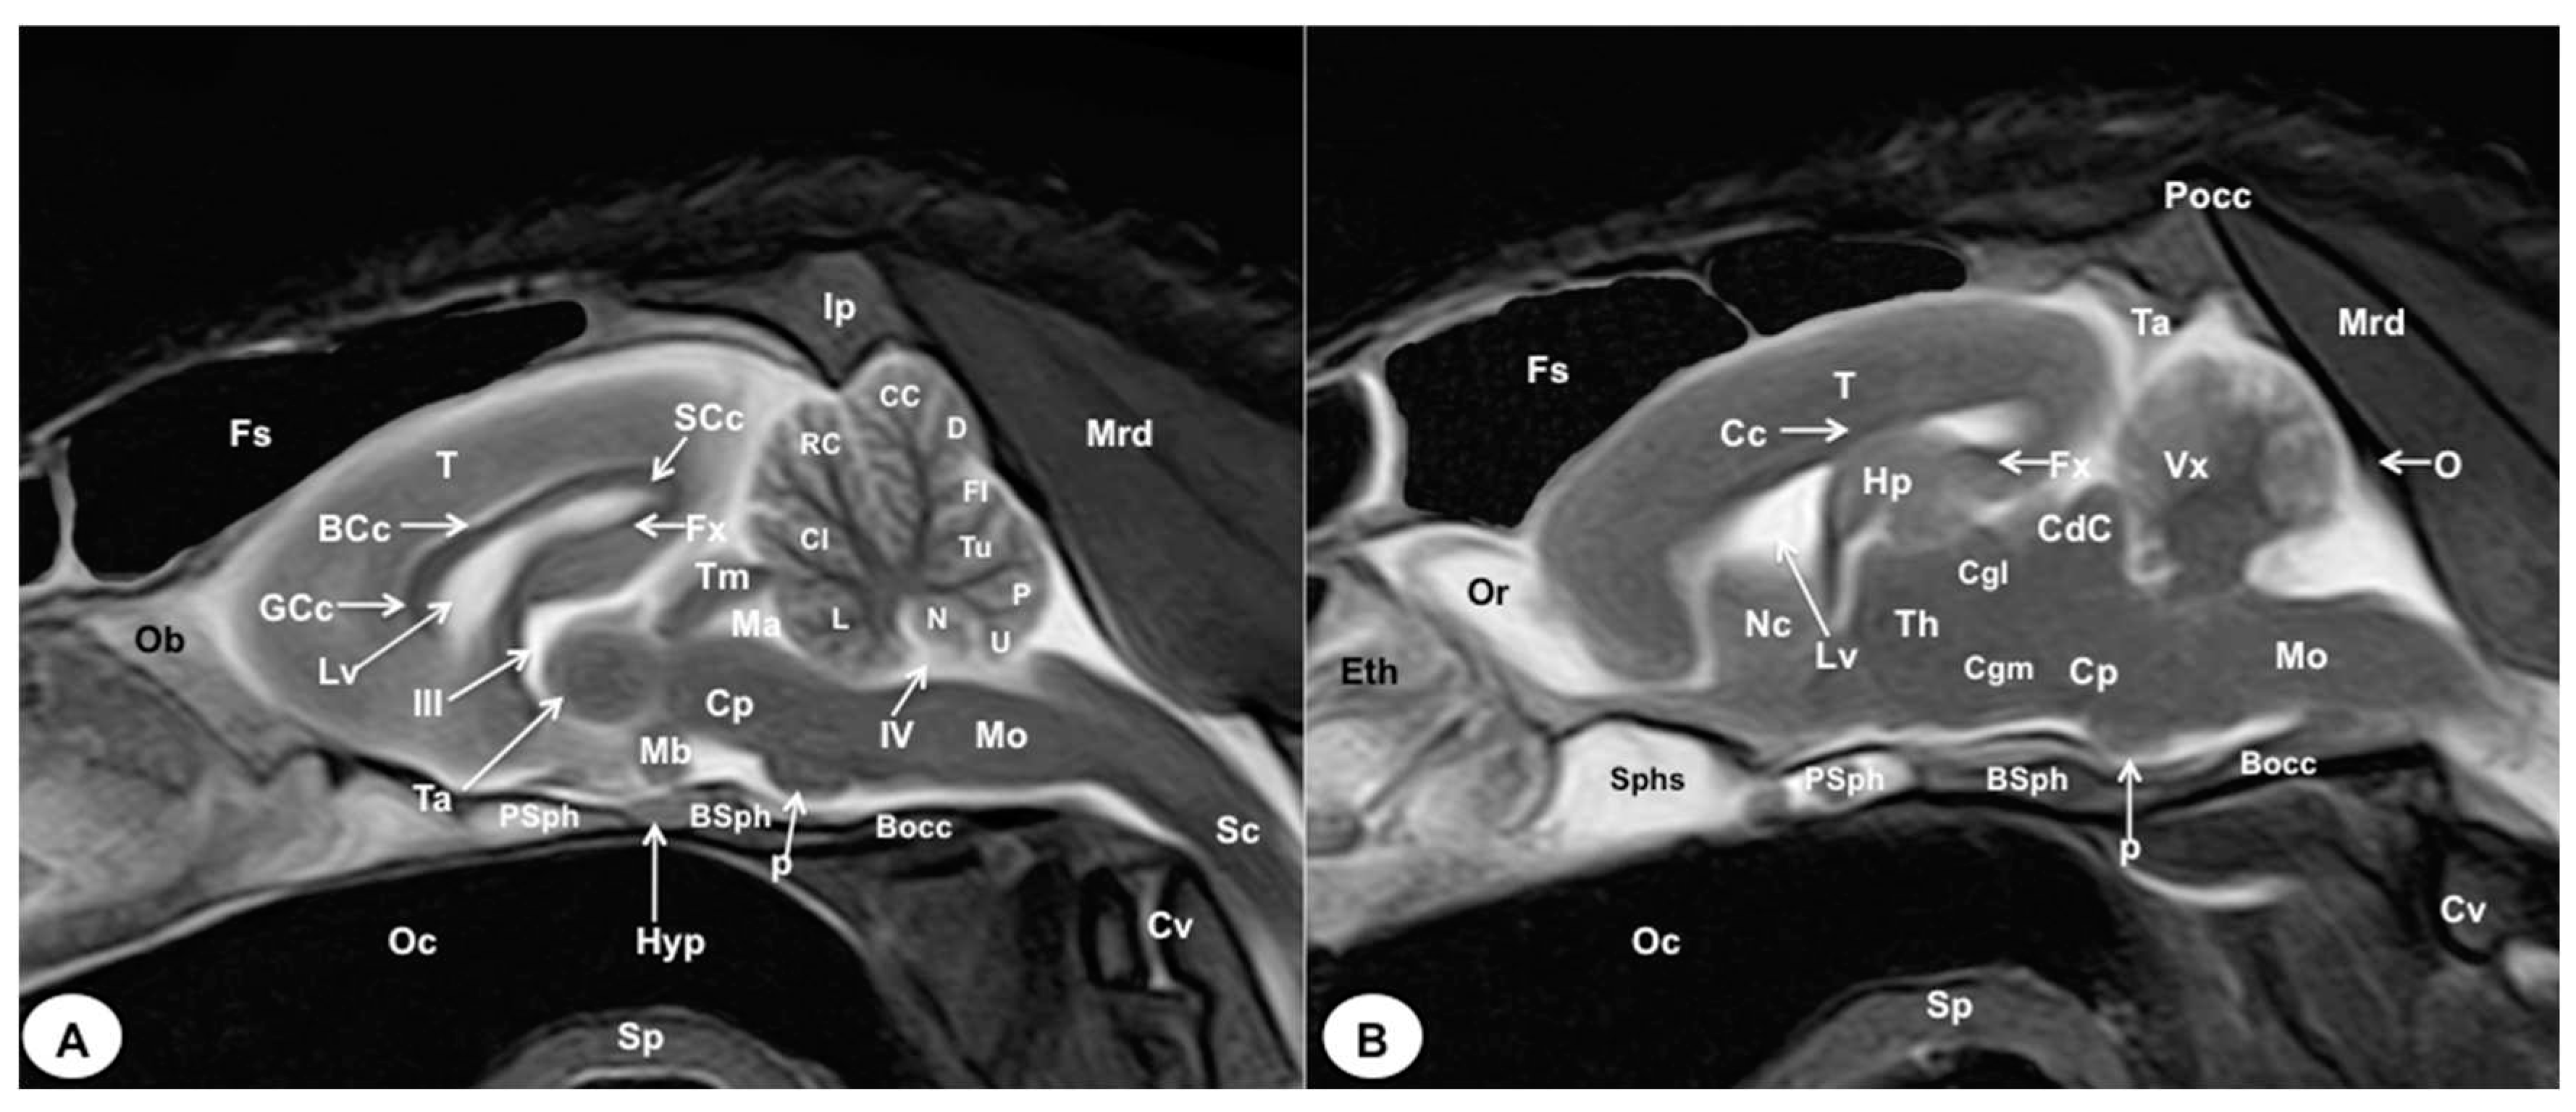

3.1. Anatomical gross-sections

3.2. Magnetic Resonance Imaging (MRI)